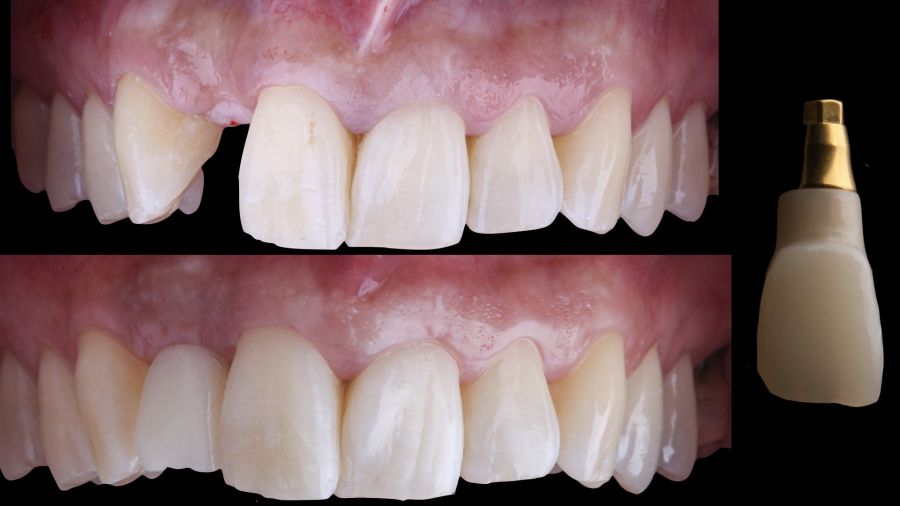

Immediate provisional restoration using a removable partial acrylic prosthesis. Phase II: guided placement of an implant and augmentation of mucosal thickness with a connective tissue graft. Phase III: shaping and modelling

of the emergence profile using a direct implant provisional prosthesis and definitive ceramic implant restoration.

* Phase III: three months after implant placement, the soft tissue condition was favourable (Figures 5 and 6). A digital impression was obtained using an intraoral scanner for the fabrication of a screwretained

polymethyl methacrylate (PMMA) provisional restoration. Regarding the definitive

implant crown, a cement-screw-retained

restoration was fabricated with a titanium nitride interface, adapting the design to the emergence profile already consolidated with the provisional prosthesis. The crown was produced by CAD-CAM in zirconia with full reduction and feldspathic ceramic veneering for zirconia (Figure 7).